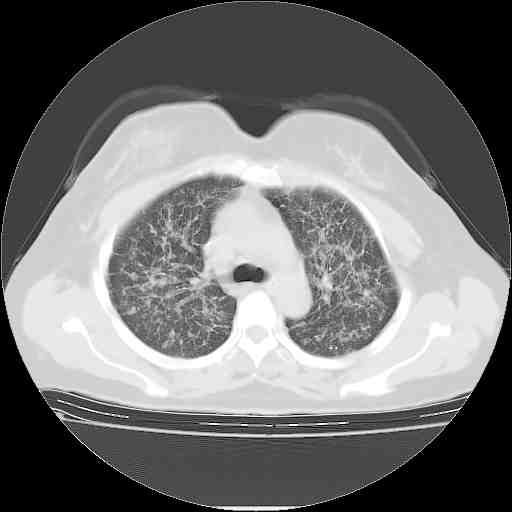

f50,肺ca治疗后,做过穿刺,确诊是肺ca,大家看看这是去年12月做的

考虑  腺癌肺内转移,治疗较前病灶缩小、减少

支持肺癌并肺内淋巴管转移,

肺癌并肺内转移,这种疾病治疗后在影像上看略有好转,不是很显著,但是肿瘤治疗效果影像只是一方面。

支持肺癌并肺内淋巴管炎,  原发灶小了,但转移较前片明显了.

支气管血管束粗而乱,考虑肺癌肺内淋巴管转移,右侧乳房第一二层软组织成份较左侧多,不会有问题吧?

支持右肺下叶周围型肺癌并肺内淋巴管炎,  原发灶小了,但转移较前片明显了.。

标准的细支气管肺泡癌呀!治疗后病情有所控制,也没治愈的迹象!